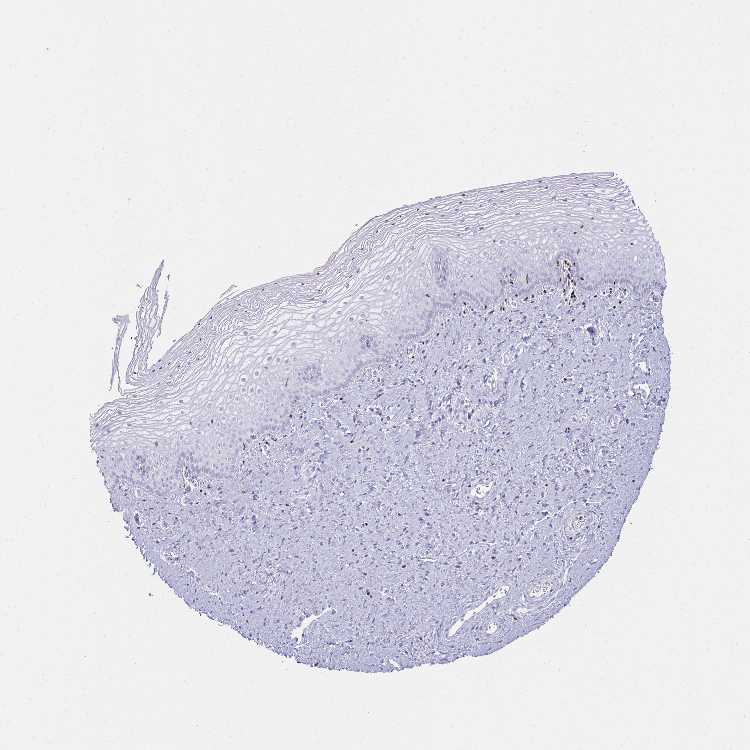

TISSUE PRIMARY DATA VAGINA Show tissue menu

Vagina

VAGINA - Antibody stainingi

Antibody staining in the annotated cell types in the current human tissue is reported as not detected, low, medium, or high, based on conventional immunohistochemistry profiling in selected tissues. This score is based on the combination of the staining intensity and fraction of stained cells.

Each image is clickable and will lead to virtual microscopy that enables deeper exploration of all samples and also displays staining intensity scores, fraction scores and subcellular localization as well as patient and tissue information for each sample.

Antibody HPA035221Antibody HPA035222Antibody CAB009247

Squamous epithelial cells Not detectedNot detectedNot detected